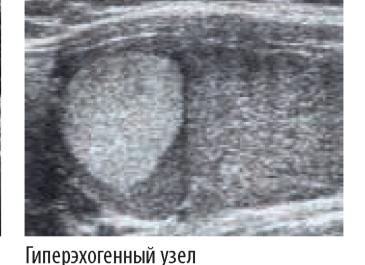

- гиперэхогенность. Данный термин обозначает плотную структуру внутреннего тела, которая намного превышает плотность окружающих тканей и очень хорошо отражает идущие волны. Чаще всего таким образом в организме диагностируются камни;

- наличие узлов и уплотнений в щитовидной железе. В норме их не должно быть (на основании результатов УЗИ). Гипоэхогенные образования щитовидной железы имеют меньшую плотность, чем окружающие ткани. Гипоэхогенные включения, наоборот, отличаются высокой эхогенностью. Гипоэхогенный узел щитовидной железы будет выглядеть на экране монитора как темное пятно. Изоэхогенные образования характеризуются такой же плотностью, как окружающие ткани. Гипоэхогенное образование щитовидной железы намного чаще имеет онкологическую природу в отличие от других типов;

Гиперэхогенный сигнал могут вызвать соли кальция, образованные на тканях щитовидной железы, вследствие нарушения электролитно-солевого обмена в организме. Гипоэхогенный узел возникает в результате структурных изменений в тканях железы. Наиболее часто этот сигнал говорит о наличии злокачественного образования щитовидной железы.